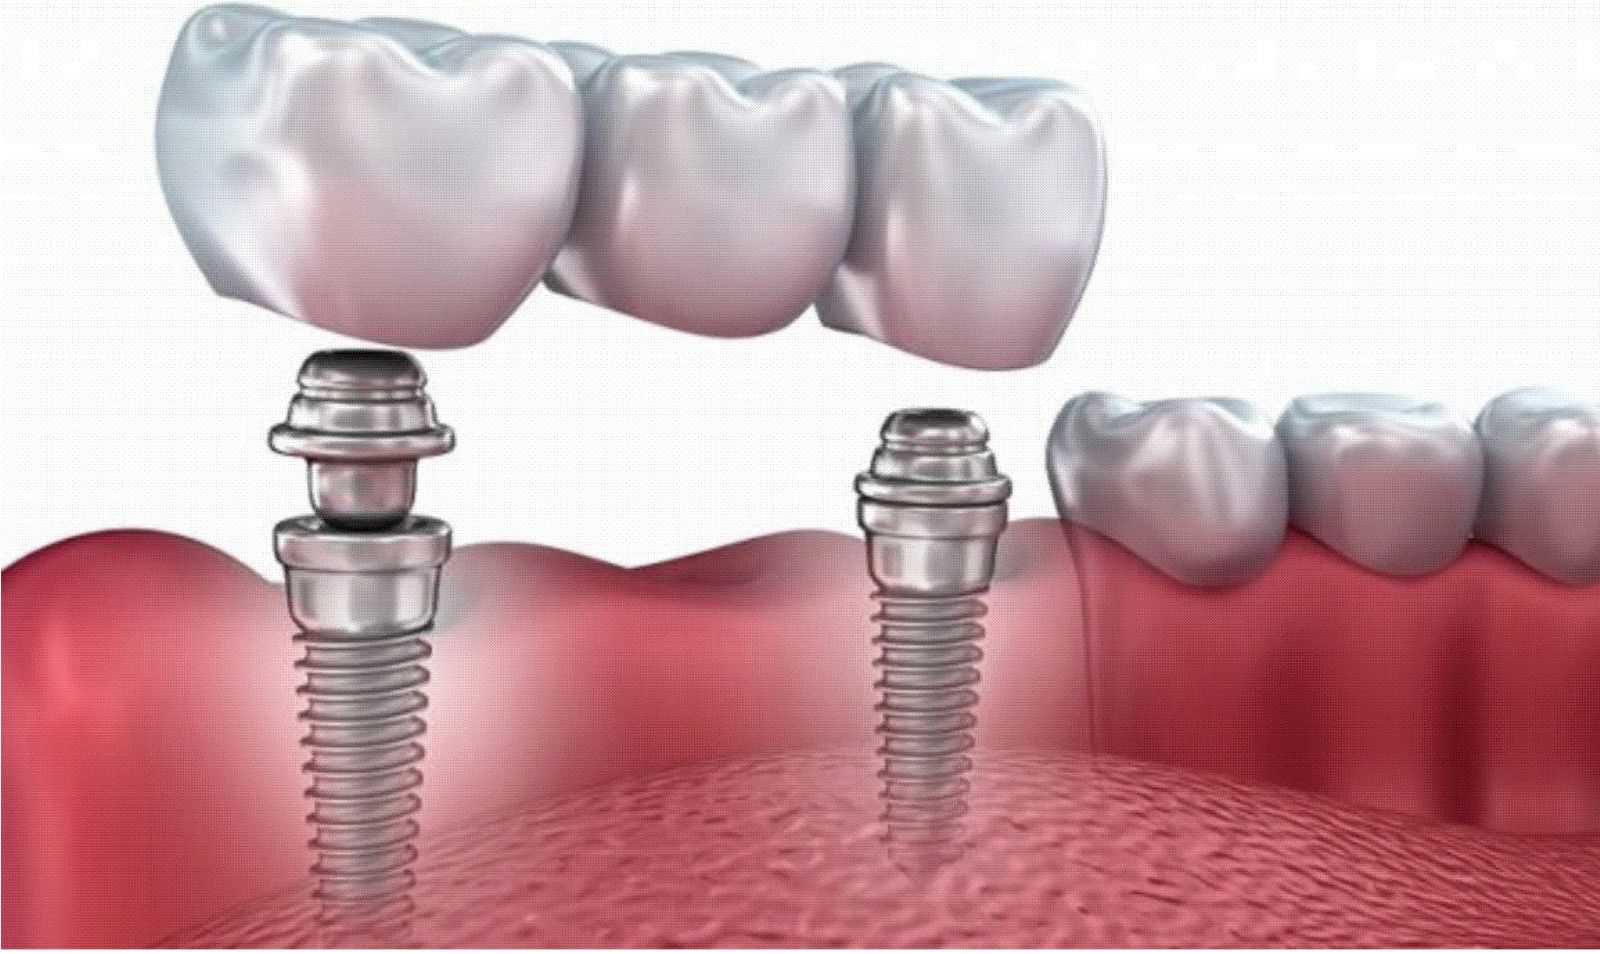

Современная стоматология: Железные зубные импланты